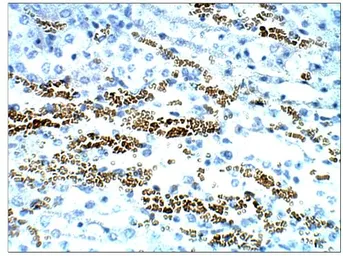

STRA6 antibody

Cat. No. GTX47858

ApplicationsWB IHC-P IP ELISA